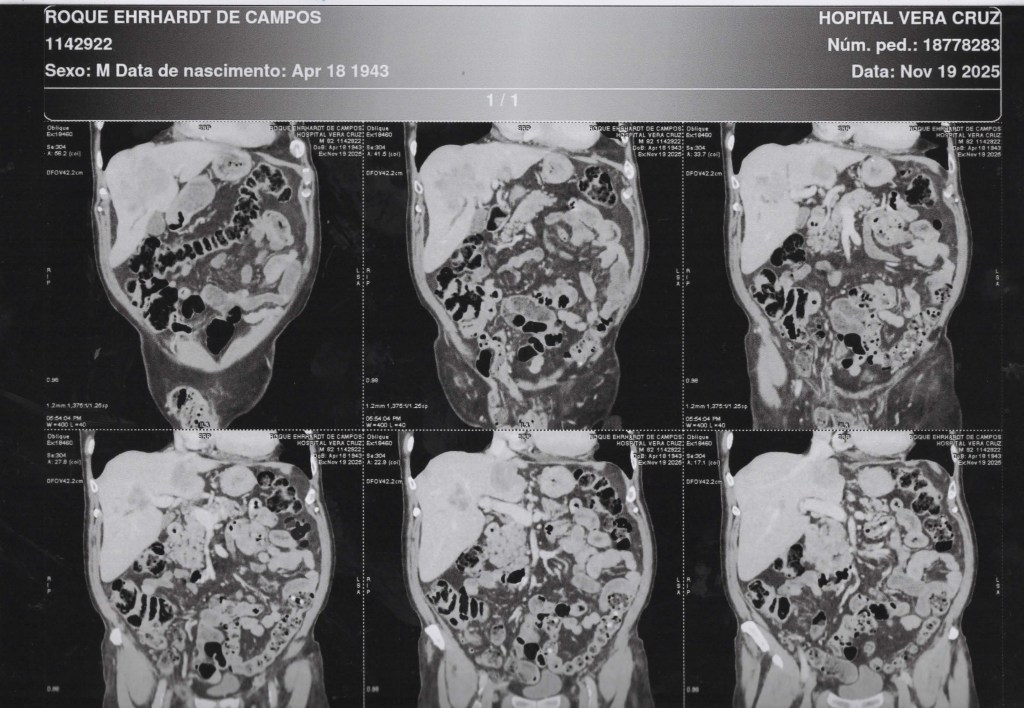

Abdome 19/11/2025 Vista Frontal